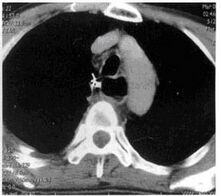

3.CT及磁共振(MRI)檢查

食管鋇餐及纖維食管鏡檢查後大部分診斷可以明確,少數病例,特別是中段平滑肌瘤,有時易與主動脈瘤、血管壓迫或畸形相混淆,行CT及MRI檢查有助於鑑別診斷。CT還可以了解腫物向管外擴展的情況及準確部位,有助於手術方案及切口的設計,B超檢查也能發現某些腫瘤。